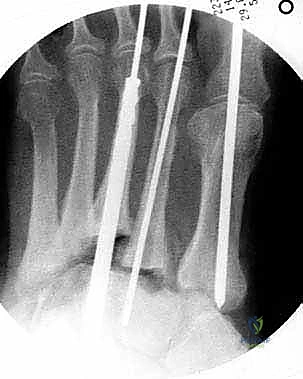

اليوم، يقود الأستاذ الدكتور محمد هطيف ثورة جراحية في اليمن من خلال استخدام تقنية "التثبيت المحوري" (Axial Beaming). تعتمد هذه التقنية على مبدأ "البناء الفائق" (Superconstruct)، حيث يتم دمج المفاصل المتضررة باستخدام مسامير معدنية صلبة وطويلة يتم إدخالها داخل التجويف النخاعي (Medullary Canal) لعظام القدم.

يتم استخدام أسلاك توجيهية (Guide Wires) يتم إدخالها تحت توجيه الأشعة السينية المباشرة (C-arm) من خلال عظام مشط القدم، مروراً بمفاصل منتصف القدم، وصولاً إلى عظام الرصغ (مثل العظم الزورقي أو الكاحل). بعد التأكد من المسار الصحيح، يتم استخدام مثقاب خاص، ثم تُدرج المسامير المحورية الصلبة (غالباً مسامير بقطر 6.5 مم أو 7.0 مم) لضغط المفاصل وتثبيتها بقوة هائلة.